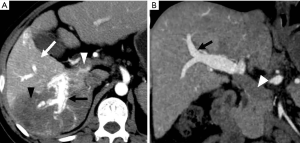

HAPS secondary to HCC may occur through the following routes: (I) transvasal: early invasion and tumor thrombi formation in the branches of the portal vein is frequent in HCC. Since the hypervascular tumor thrombi are supplied by the vasa vasorum of the portal vein wall (21), hepatic arterial flow may drain into the lumen of the portal vein from tumor thrombi (11). These usually manifest as a central and severe HAPS (Figure 5). (II) Transplexal: HCC may sometimes be associated with compromised portal vein flow, and a subsequent HAPS via the transplexal route may be involved (2,16). Arterial blood shunts to the portal venous and hepatic sinusoids via the peribiliary plexus in these cases and usually presents with moderate HAPS (Figure 6). (III) Transsinusoidal: less frequently, retrograde arterial blood shunts into branches of the portal vein via the hepatic sinusoids because of the compromised hepatic venous flow in HCC, which generally constitutes a mild and peripheral HAPS. (IV) Transtumoral: the arterial blood supply to the HCC can be shunted through the tumor venous into peripheral portal veins (10).

Evaluation of HCC with HAPS

HAP results in the heterogeneous enhancement of the hepatic parenchyma. The enhancement of HCC will be significantly reduced in the situation of serious HAPS due to a large amount of contrast medium flowing into the portal vein through the shunt. On the equilibrium phase, the characteristic washout and extension of the tumor can nonetheless be identified accurately. The equilibrium phase is most useful for diagnosis and delineation of HCC as an area of heterogeneous low density (intensity) (Figures 7,8). The presence of HAPS is not necessarily a contraindication to resection, ablative therapies or other liver-directed therapies, and the degree of resection or other therapy can best be determined in the equilibrium phase (22).